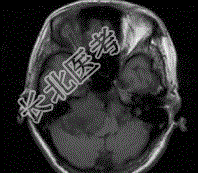

- 单项选择题女,45岁, 右耳听力下降半年余,CT检查如图, 最可能的诊断是